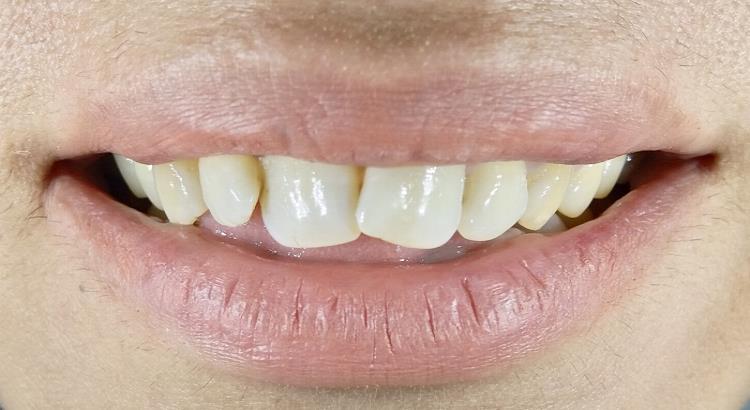

Güvenebileceğiniz Sonuçlar